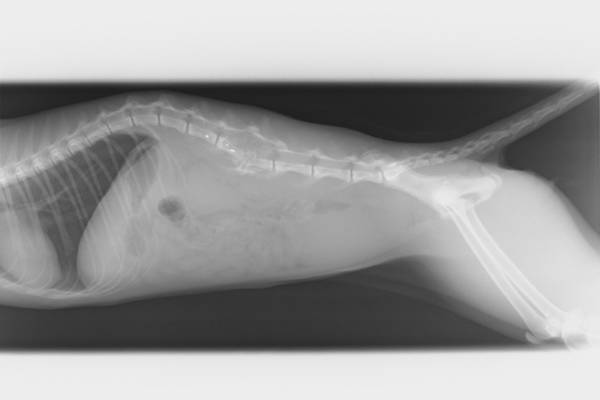

Tanna (ots) - Im Zeitraum vom vergangenen Freitag bis Montag wurde eine Katze durch einen Unbekannten angeschossen und so schwer verletzt, dass sie eingeschläfert werden musste. Die Halterin hatte im Rahmen der Anzeigenerstattung berichtet, dass ihre 1,5 jährige Katze, welche Freigänger ist, seit dem Abend des 24.07.2020 aus dem Stickereiweg in Tanna vermisst wurde. Gegen Montagmittag erhielt sie nach umfangreicher Suche einen Hinweis, dass sich eine augenscheinlich verletzte Katze in einem Lichtschacht unweit ihres Anwesens, ebenfalls im Stickereiweg, befindet. Die Vermutung bestätigte sich: Es handelte sich um die gesuchte Katze- augenscheinlich unfähig, sich zu bewegen und in den eigenen Exkrementen liegend. Die Tierhalter verbrachten sie umgehend zum Tierarzt nach Schleiz, dort wurde festgestellt, dass die Katze einen Durchschuss im Bereich der Wirbelsäule erlitten hatte, welcher nicht behandelbar war. Schweren Herzens entschlossen sich die Besitzer, das Tier von seinem Leiden zu erlösen und hoffen nun auf Zeugenhinweise aus der Bevölkerung. Das Tier könnte im Bereich des Stickereiweges oder aber auch im nahen Umfeld angeschossen worden sein- aufgrund der Schwere der Verletzungen und den damit einhergehenden Fortbewegungsschwierigkeiten wird ein Tatort in großer Entfernung nahezu ausgeschlossen. Gemäß §17 des Tierschutzgesetzes können Beschuldigte, welche ein Tier grundlos töten oder ihm erhebliche Schmerzen/Leiden zufügen, mit einer Freiheitsstrafe bis zu drei Jahren oder mit Geldstrafe bestraft werden. Bei verdächtigen Wahrnehmungen, sachdienlichen Hinweisen zum Vorfall oder aber wenn Ihrem Tier ähnliches widerfahren ist, wenden Sie sich an die zuständige Polizeidienststelle, in diesem Fall an die PI Saale-Orla unter 03663-4310. Das Geschoss wurde bislang nicht aufgefunden- der Umfang wird auf etwa 4,5 mm geschätzt. Es ist bislang unklar, ob die Munition eines Luftdruckgewehres, oder aber ein Gewehr mit größerer Durchschlagskraft, den Durchschuss verursacht haben könnte. Die Besitzerin stimmte der Veröffentlichung des Röntgenbildes sowie einer Aufnahme der Verletzung zu.